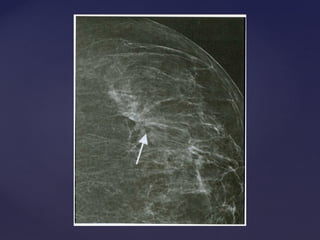

Descrição dos achadosDescrição dos achados

Distorção focal de arquitetura

Descrição dos achadosDescriçãodos achados Distorção focal de arquitetura